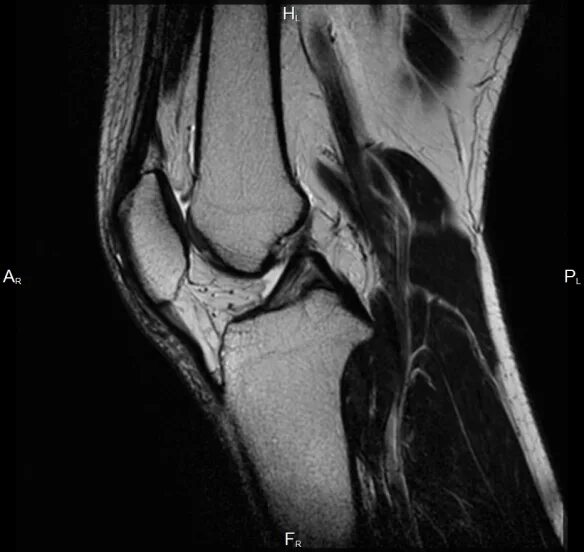

Мрт коленного сустава набережные